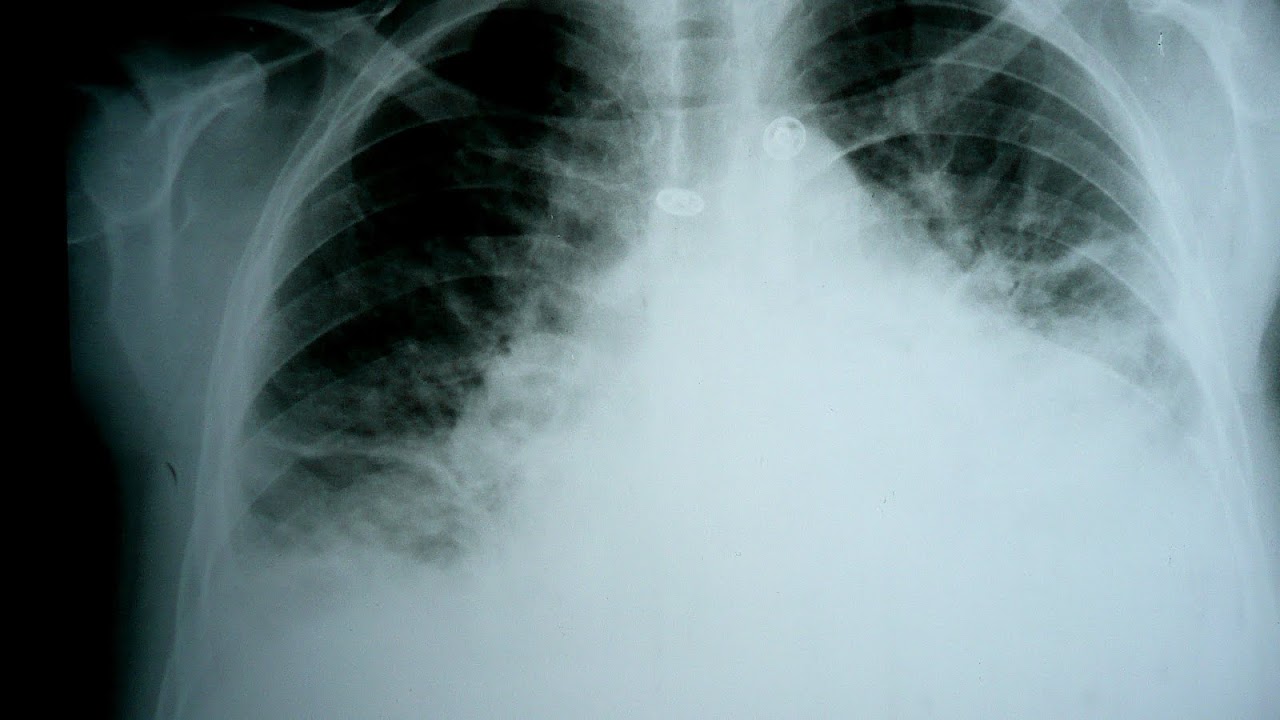

Chest X-ray

Chest X-rays are frequently used to aid in the diagnosis of CHF. In a person who is compensated, this may show cardiomegaly (visible enlargement of the heart), quantified as the cardiothoracic ratio (proportion of the heart size to the chest). In left ventricular failure, there may be evidence of vascular redistribution ("upper lobe blood diversion" or "cephalization"), Kerley lines, cuffing of the areas around the bronchi, and interstitial edema. Ultrasound of the lung may also be able to detect Kerley lines.